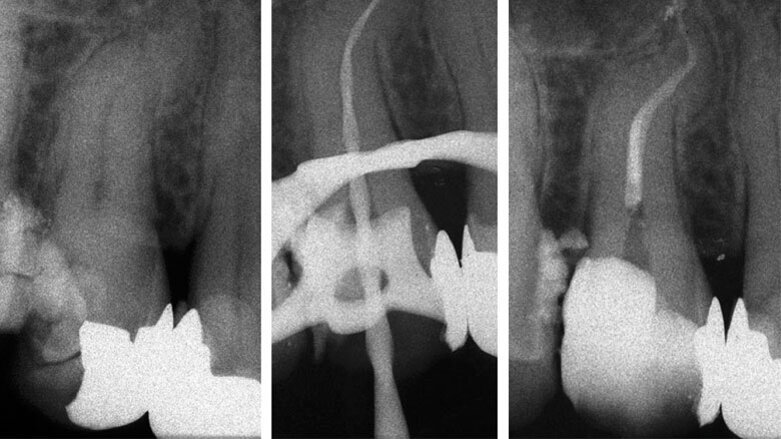

All’esame radiografico le otturazioni appaiono dense ed omogenee, la guttaperca mostra un buon adattamento alla morfologia endodontica, determinando un buon riempimento delle irregolarità del sistema canalare. Sono stati evidenziati la presenza di canali laterali ed uscite apicali multiple. Figg. 8a-8e molare superiore, Figg. 9a-9e molare inferiore, Figg. 10a-10c molare superiore, Figg. 11a-11d anatomie complesse premolare curvo e Figg. 12a-12d ottavo.

Fig. 1- Ritrattamento canalare 3.6 controllo a 5 anni.

Fig. 8 - Terapia canalare 1.6 controllo a 17 anni.